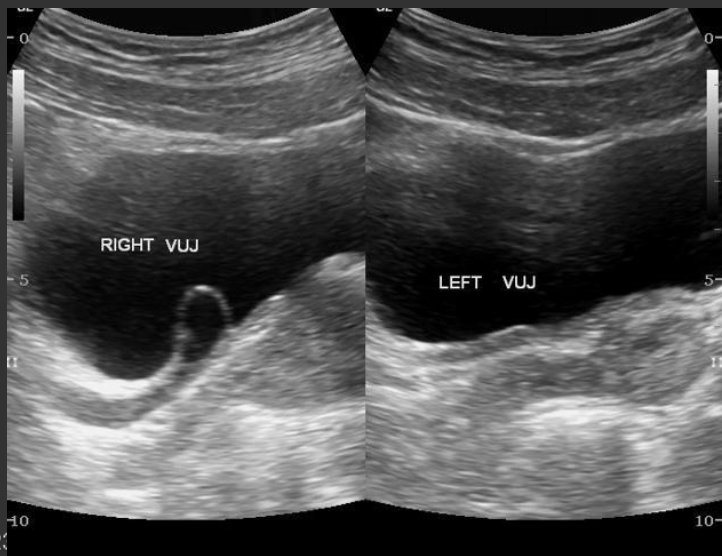

VUR (Vesicoureteral Reflex) → common, non-obstructive cause of hydronephrosis (reflux of urine from bladder back up ureters into kidney)

2D US: hydronephrosis, intermittent dilations of collecting system (post-void changes), displaced ureteral jet in bladder, ureterocele (ballooning of lining of ureter into bladder)

color doppler: avascular

DDX: